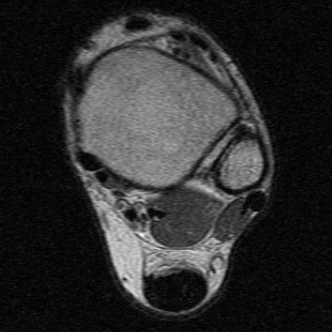

MRI

Tendon thickening

Thickening of the tendon with some intra-substance degeneration / partial tearing